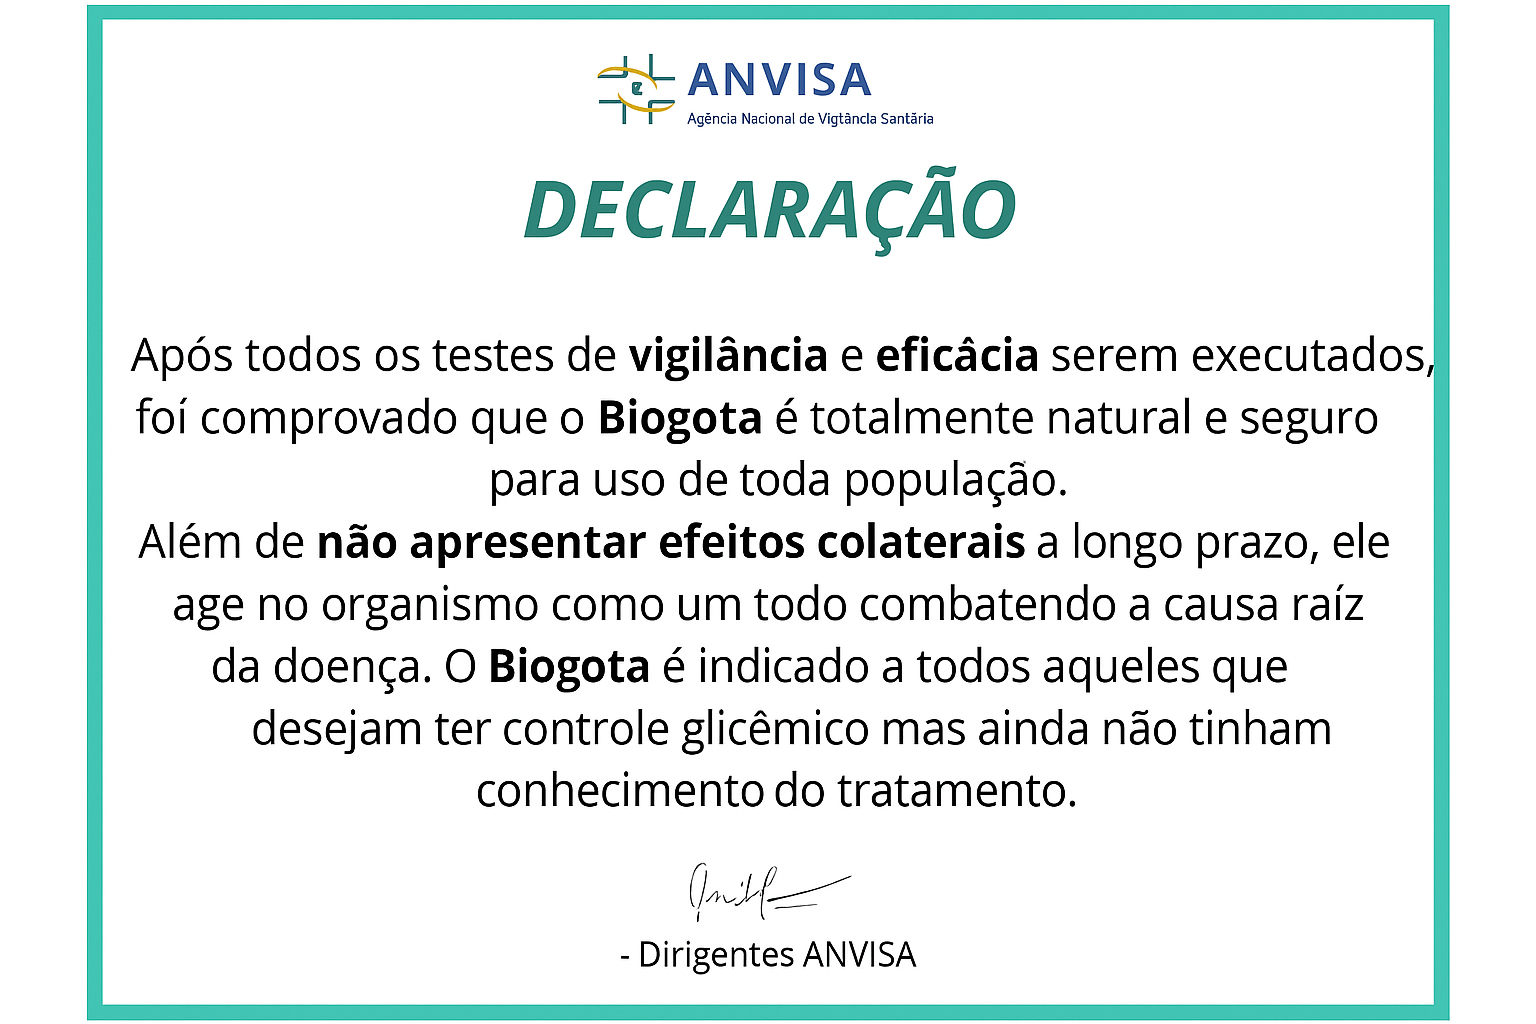

Drauzio Varella: Dra Yumi, esse tratamento já foi aprovado pela ANVISA aqui no Brasil?

Dra. Yumi Tensai: Sim, a gente enviou três lotes totalmente gratuitos para o Brasil em 2024, inclusive um foi para testes na ANVISA!